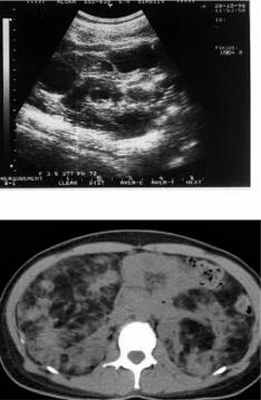

УЗИ. Кисты почки

На КТ множественные двусторонние образования в почках, содержащие жировую ткань – ангиомиолипомы.